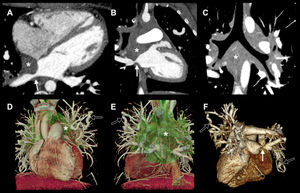

Se presenta el caso de una mujer de 19años con disnea progresiva. La angiotomografía computarizada reveló una masa hipodensa infiltrativa en el espacio visceral mediastínico que no realza con contraste y que envuelve la vasculatura pulmonar y los bronquios (fig. 1A-E, asterisco). Esto causó estrechamiento tanto de las arterias como de las venas pulmonares (fig. 1A,B,F, flechas sólidas), con dilatación postestenótica y numerosas colaterales venosas (fig. 1D-F, flechas huecas), lo que sugiere mediastinitis fibrosante. Se diferenció de la tromboembolia crónica en que las lesiones son típicamente intravasculares e incluyen defectos parciales excéntricos, redes o bandas, con zonas de estenosis principalmente focales en arterias generalmente segmentarias y ausencia de compromiso de la circulación venosa.